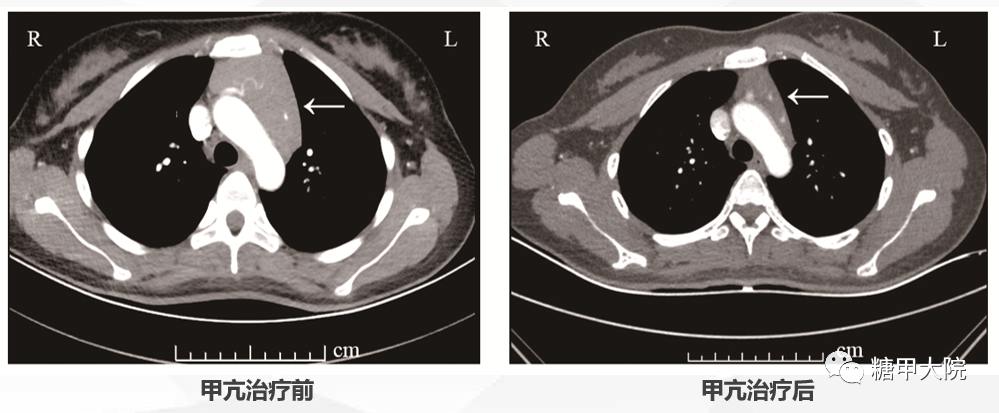

01 病情回顾 患者,女性,22岁。因“怕热、多汗、心悸1月余”入院。1月余前当地医院经甲状腺功能、甲状腺抗体和甲状腺超声等检查,明确诊断患者为“Graves病”,服药前患者肝功能轻度异常,未予保肝治疗。给予甲巯咪唑?10mg?qd、美托洛尔缓释片 47.5mg?qd治疗,4日后复查肝功能提示转氨酶明显增高,肝损较前明显加重,当地医院予停甲巯咪唑和美托洛尔缓释片,同时给予口服保肝药物治疗,另外予普萘洛尔?10mg?tid?控制心率。因肝损严重,当地医院建议同位素碘治疗Graves病甲亢。 因为患者甲状腺功能指标中的游离T3(FT3)和游离T4(FT4)均明显增高,大于正常值上限,核医学科考虑患者甲亢病情重,同位素碘治疗有风险,建议先内分泌科治疗,待甲亢病情稳定后再考虑同位素碘治疗。故将患者收入上海市第六人民医院内分泌科特需病房进一步治疗。 02 病情变化 身高 166cm,体重 56.1kg,P 105次/分,BP 111/66mmHg,BMI 20.36kg/m2。全身皮肤无潮湿,轻度突眼,眼球活动自如,无瞬目减少,辐辏反射正常,气管位置居中,甲状腺2度肿大,质韧偏软,活动度好,无压痛,未触及结节,甲状腺部位无震颤,无血管杂音,双手水平细颤阳性。 既往病史无特殊,近2月月经量少,周期正常。 入院后进行了详细的实验室及器械检查,根据检查结果,Graves病诊断比较明确,肝功能和中性粒细胞基本都正常。入院后甲状腺及颈部淋巴结超声的结果如下: 根据患者的检查结果,调整保肝药物继续保肝治疗,同时给予甲巯咪唑 15mg qd 治疗,普萘洛尔剂量加大,改为 20mg?tid。患者服药后心慌症状缓解,入院后第5天查房时患者主诉有较明显的恶心,时有呕吐。当时我们考虑患者是否服用甲巯咪唑后又出现了严重的肝功能损害,给予急查血常规、肝肾功能和血电解质,同时暂停服用甲巯咪唑。 检查结果出来后,出乎我们的意料,患者的血常规、肝肾功能均正常。但出现了较严重的高钙血症。结果如下: 患者入院时常规血电解质检测,血钙轻度增高为2.65 mmol/L,当时考虑甲亢本身会引起高钙血症且血钙轻度增高,故未予特殊处理。但是根据最新的检查结果,血钙明显增高,考虑患者恶心、呕吐等消化道症状应该是高钙血症导致的,与肝功能损伤没有关系,故继续甲巯咪唑服用,剂量不变,仍为 15mg qd,同时给予补液水化等降血钙治疗。 高钙血症最常见的原因主要是甲状旁腺功能亢进和恶性肿瘤。故针对高钙的原因又补充了一系列检查,发现患者甲状旁腺激素明显降低,尿钙排出明显增高,结果如下: 因为甲状旁腺激素明显降低,考虑是高钙引起的甲状旁腺激素抑制,而且甲状旁腺扫描(甲状旁腺ECT)也未发现甲状旁腺部位、纵隔区及其他部位放射性浓聚。故原发性甲状旁腺功能亢进症基本排除。甲状旁腺扫描结果如下: 因为排除了原发性甲旁亢,故我们后续的检查主要聚焦于恶性肿瘤的排查。但肿瘤标记物、骨髓穿刺、血清免疫固定电泳均正常;全身骨显像也未见明显异常。 但在检查过程中,发现了两个明显异常的检查结果:严重骨质疏松和胸腺明显增大。因为患者年龄仅22岁,所以目前的骨密度对于患者来说是相当低的,部分骨代谢指标检测结果如下:骨钙素 51.46ng/mL?增高(正常范围 11-46);B-胶原特殊序列 (βCTX) 2105.00 ng/L?增高(正常范围 < 573)此外,根据胸部CT图像,我们初步计算了胸腺的体积,根据相应的公式,胸腺体积达到?1963.58mm2。相应结果如下: 根据检查结果,我们当时高度怀疑胸腺增生是否与高钙血症和骨质疏松有关,因为有文献报道,胸腺本身可以分泌PTH相关肽(Parathyroid?hormone-related?peptide,?PTHrP)?引起骨吸收增加而出现高钙血症和骨质疏松,因此我们曾打算给患者行胸腺穿刺以明确诊断,必要时考虑胸腺切除手术治疗。 但是考虑到患者甲亢未完全控制,而且也无法确定胸腺增生与高钙是否一定相关,另外,经过补液水化等治疗,患者的血钙水平也已经下降;最后,Graves病本身也有引起胸腺增生的可能,故暂缓胸腺穿刺。继续予甲巯咪唑 15mg qd 治疗甲亢、保肝药物保肝治疗,密切监测电解质,嘱患者出院后定期随访观察。出院时血钙明显下降,基本接近正常,结果如下: 甲亢治疗4周后患者甲功有所改善,血钙恢复至正常范围。继续给予抗甲状腺药物治疗,患者甲状腺激素和TRAb水平逐渐下降;PTH也逐渐上升至正常范围;血钙和血磷水平保持在正常范围。后续治疗过程中保肝药物也逐渐减量,最后停用。 患者甲亢治疗8月后,患者骨密度有改善,L1-4骨密度-2.4g/cm2,颈部骨密度-0.7g/cm2。让我们意外且欣喜的是,患者复查胸部CT显示明显肿大的胸腺已经明显缩小,经过公式计算,胸腺体积已经缩小至?911.01mm2,治疗前后的CT结果比较如下: 甲亢治疗14个月后,患者复查甲状腺功能、TRAb、骨代谢指标及骨密度结果如下:? 在整个治疗过程中,甲亢控制后,患者血钙一直保持在正常范围内。 目前患者还一直在糖甲大院李医生这里随访,目前服用甲巯咪唑 5mg qd 控制甲亢,甲状腺功能指标一直控制在比较理想的范围内,TRAb也已经恢复正常,但最近本院刚开展的检测项目-促甲状腺激素受体刺激性抗体(TSAb)还稍微偏高,结果如下: 03 病情分析 根据入院后一系列检查,Graves病甲亢、药物性肝功能损害诊断明确。但巨大胸腺增生、明显高钙血症、严重骨质疏松大尤其是胸腺增大的原因当时无法明确。甲亢可以引起高钙血症、骨质疏松及胸腺增生,但巨大的胸腺增生很罕见。这三者间是不是存在某种联系?会不会增大的胸腺分泌某些物质引起高钙血症和骨质疏松?查阅文献,胸腺确实会分泌PTH相关肽而引起高钙血症。当时我们也怀疑巨大的胸腺是不是高钙血症的原因,也打算是否考虑胸腺穿刺活检以明确胸腺病变。 我们在随访观察中,发现随着甲亢的好转,患者血钙降至正常,而且治疗过程中FT3及FT4水平与血钙呈显著正相关,提示甲亢是导致高钙发生的原因,结果如下: 另外,甲亢治疗控制后患者的骨质疏松、胸腺增大均明显好转,也提示甲亢是导致患者骨质疏松和胸腺增大的根本原因。至此,经过长时间的随访观察,通过甲亢治疗后患者高钙血症消失、骨质疏松缓解、胸腺增生明显缩小,推断甲亢是引起这一系列症状的根源。 04 可能机制 据报道,大约20%的甲状腺功能亢进症患者可能伴轻度至中度的高钙血症。极少数甲亢患者可能会出现高钙危象。甲亢时甲状腺分泌过多的甲状腺激素,甲状腺激素对钙磷代谢有双重作用。一方面,甲状腺激素可以抑制甲亢患者体内活性维生素D的水平,肠道和肾脏对钙和磷的吸收降低,而肾脏对钙和磷的排泄又增加。另一方面,甲状腺激素可以加速骨转化,特别是破骨细胞活性增加,从而导致血钙水平的增高。 本病例罕见之处在于:明显高钙血症、严重骨质疏松和巨大胸腺增生同时发生于Graves病甲亢患者。病例给我们的启发很多,临床医生在诊断治疗临床常见疾病时不可忽视常见疾病少见症状的存在及处理,否则可能造成漏诊和误诊,短时间内无法明确诊断时,在病情允许的情况下随访观察病情变化也许是一个比较明智的解决办法。 最后,糖甲大院李医生还是要和各位分享一下自己的心得体会。 ?Yan D, Xu Y, Li LX.The coexistence of hypercalcemia, osteoporosis and thymic enlargement ingraves' disease: a case report. BMC Endocr Disord. 2020.?20(1): 97. Medas F, Erdas E, Loi G, et al. Intraoperative parathyroid hormone (PTH) testing in patients with primary hyperparathyroidism and PTH levels in the normal range. BMC Surg. 2019;18(Suppl 1):124. Williams GR, Bassett JHD. Thyroid diseases and bone health. J Endocrinol?Investig. 2018;41(1):99–109. Ryan CS, Petkov VI, Adler RA. Osteoporosis in men: the value of laboratory?testing. Osteoporos Int. 2011;22(6):1845–53. Gunn A, Michie W, Irvine WJ. The Thymus in Thyroid Disease. Lancet. 1964;?2(7363):776–8. Dalla Costa M, Mangano FA, Betterle C. Thymic hyperplasia in patients?with?Graves' disease. J Endocrinol Investig. 2014;37(12):1175–9. Gessi M, Monego G, Lauriola L, Maggiano N, Ranelletti FO. Parathyroid hormone-related peptide (hPTHrP) and parathyroid hormone-related peptide receptor type 1 (PTHR1) expression in human thymus. J Histochem Cytochem. 2005;53(8):955–62.